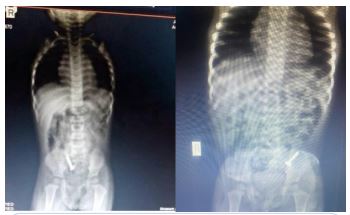

She presented with a plain abdominal radiograph which showed a FB (nail) in the body of the stomach (Figure 1) This was done about 6 hours prior to the presentation at our facility. A repeat radiograph done at the presentation showed the FB (nail) at the region of the terminal ileum (Figure 2). She was commenced on nil per oral, intravenous fluids and monitoring (clinical and radiological). She had two additional plain abdominal radiographs, (Figure 3, 24 hours on admission) and (Figure 4, on day 3). The vital signs remained stable and the abdominal examinations remained equivocal throughout the period of admission. She was discharged following a repeat radiograph which showed no evidence of FB in the GIT.

Figure 1: AP view of plain abdominal radiograph (6 hours prior to presentation).

Figure 2: AP + Lateral view of plain abdominal radiograph. (Done at presentation).